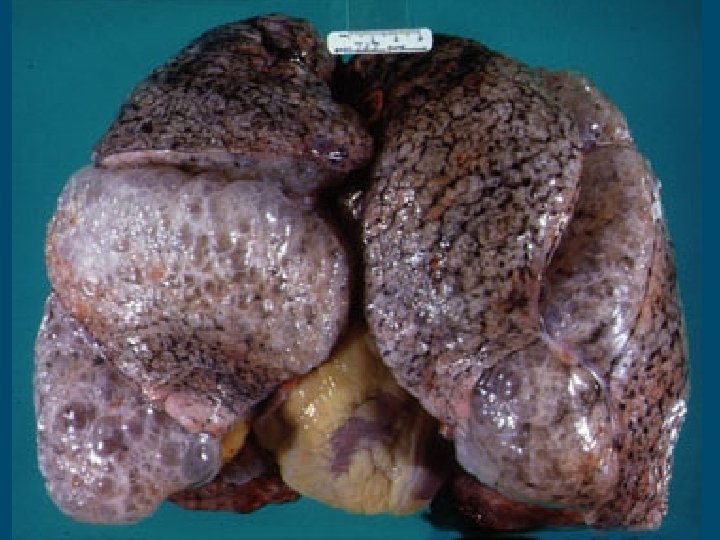

Emphysema § A disease that progressively destroys the walls of the alveoli. § Almost always caused by smoking. § Some symptoms include breathing difficulty and chronic cough. § Behavioral factors – smoking, choice of occupation § Environmental factors – general pollution, asbestos in buildings, secondhand smoke